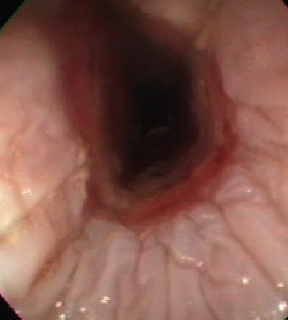

how can endoscopy be helpful for diagnosing choke in horses?

for more complicated cases, can help visualize obstruction, assess mucosa, and retrieve material

1. ideally perform endoscopy to assess mucosa

endoscopy, barium swallow studies

with endoscopy